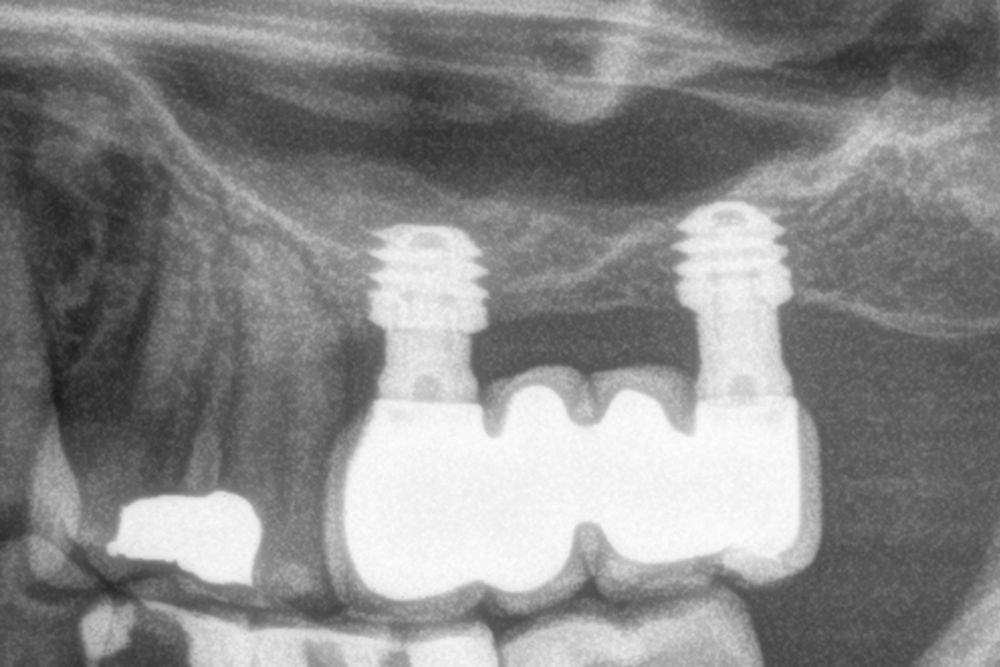

Material and method. A retrospective study has been carried out in patients in whom extra-short implants (4.5 and 5.5 mm length) were inserted directly by transcrestal elevation with residual ridges between 2 and 3 mm. The implant was the analysis unit for the descriptive statistics regarding location, implant dimensions, and radiographic measurements. The patient was the measurement unit for the analysis of age, sex and medical history. The main variable was the gain in height over the apex of the implant after 6 months of the surgery and one year after the load comparing both measurements and as secondary variables the biological complications and the implant failure were recorded.

Results. Ten patients who met the inclusion criteria were recruited and 20 implants were inserted. The mean residual bone volume height was 3.1 mm (+/- 0.3 mm with a range elevation above the apex of the implant in millimetres is of 2.8 mm (+/- 0.99 range 1.9 -5 mm). In the control cone-beam after one year of the studied load of the implants, the bone gain achieved was maintained, with no decrease in the volume gained, only three cases showed a decrease of between 0.4 and 0.5 mm of the initial volume at the end. No implants failed in the follow-up period and no biological complications were found in the surgery.

Conclusions. Achieving success of implants placed in areas of extreme horizontal atrophy by transcrestal sinus approach with extra-short implants is possible, provided that a correct stabilization of the implant is achieved in the initial phase (primary stability) and a careful milling protocol is used, insertion of the implant, graft management, 100% processing of bone and autologous plasma and subsequent loading of the same (progressive load).